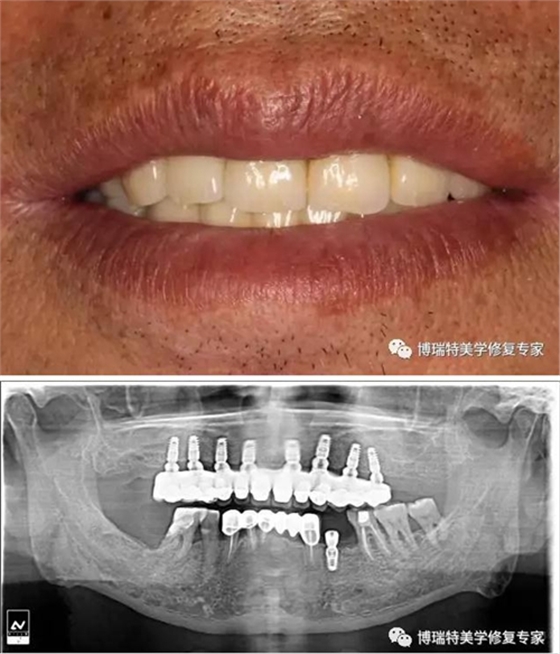

螺絲固位基臺修復便于操作,但程序相對復雜,比較普遍的還是使用二次印模法完成,大致流程如下:

患者口內(nèi)閉合式轉(zhuǎn)移桿取模,托盤和替代體送技工所;

技師完成石膏模型的翻制;在石膏模型上安裝開窗轉(zhuǎn)移桿,并通過樹脂將開窗轉(zhuǎn)移桿連接到一塊;

用樹脂連接的開窗轉(zhuǎn)移桿寄回門診;

醫(yī)生從連接兩個開窗轉(zhuǎn)移桿的樹脂中間處切斷,并把每個轉(zhuǎn)移桿依照模型上的排列單獨在患者口內(nèi)安裝到位。再次使用樹脂將轉(zhuǎn)移桿連接。這些工作主要是為了確保取模的準確性;

二次取模完成的印模寄給技工所,技師在此基礎上完成最終模型,并在此模型上完成上部冠的制作,義齒制作完成后寄回門診;

醫(yī)生完成最終修復體的安裝。